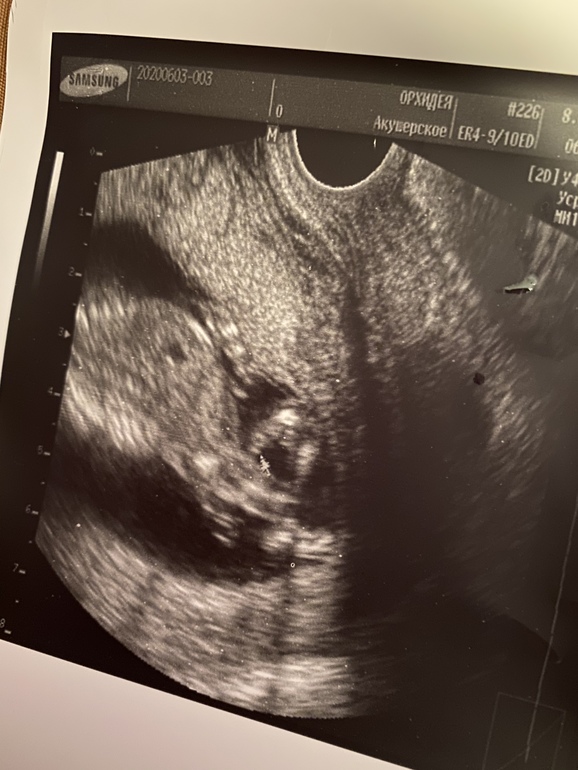

УЗИ, КТГ, доплеркакой пол вам кажется?) узист сделал предположение, но не уверен . Знаю что рано, но кому то на этом сроке точно говорят((

Это мальчик))Прям конкретный такой))

Вам с мальчиками говорили и показывали на таком сроке? Просто не понятно, узист по половому бугорку сначала говорит девочка похоже, а потом увидел что торчит и говорит мальчик

Мальчиков вообще видно сразу)У вашего между ног не перепутать уже)))